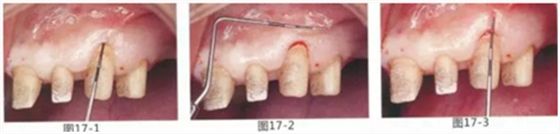

圖17-1~3 左上3的牙周袋探測值為3mm,角化牙齦寬度為2mm。也就是完全不存在附著齦,如果這種狀態(tài)下佩戴修復(fù)體的話,很有可能發(fā)生頸部暴露等問題。